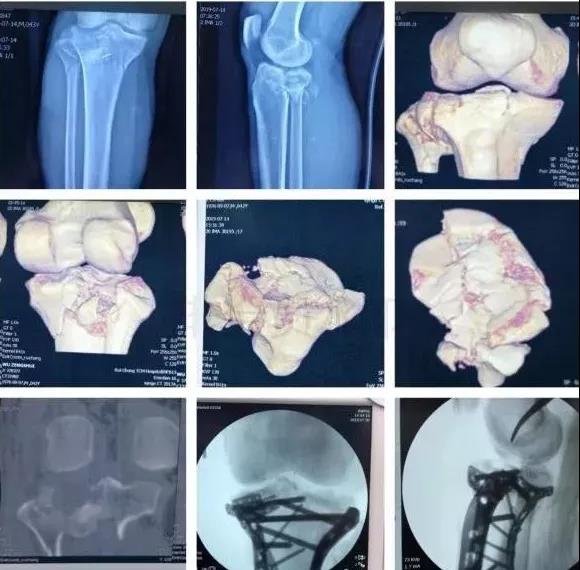

5)胫骨近端骨折(平台)

- 确定损伤机制,暴力损伤程度。

- 排除骨筋膜室综合征及血管,神经损伤。

- 高能量损伤,皮肤软组织条件差的,应延期手术。